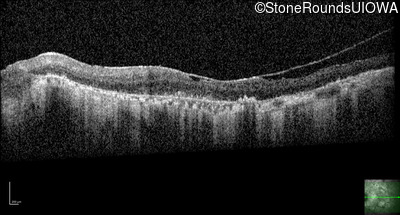

Type 1 Usher Syndrome (IB1a)

Age at visit: 62 years

This 62 year old man has had profound hearing loss since birth and has communicated using sign language for his entire life. He first noticed a problem with his vision at about age 11 when he noticed night blindness and began to trip over objects that he should have seen.